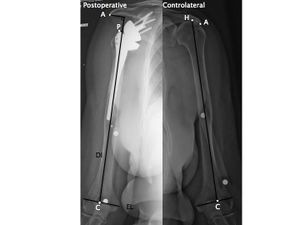

From a clinical perspective lengthening of the arm and humerus, distalization angle, acromio-prosthesis distance (Figures) have been used as surrogates for deltoid tension since they intuitively correlate with deltoid tension and they have been correlated with functional outcome and risk of postoperative instability.[29][30][28] Most of these factors nowadays can easily be evaluated thank to navigation software.[31][32]

The epicondylar line (EL) is defined between the most lateral part of the medial and lateral epicondyle. Another line, the diaphyseal axis (DI), is determined by a line drawn in the centre of the proximal medullary canal. Intersection between the epicondylar line and the diaphyseal axis represent the point C. Intersection between the diaphyseal axis and top of the humeral head is named H. The point A is located at the intersection between the diaphyseal axis and a perpendicular line passing through the most lateral and inferior point of the acromion. A, C, and H are represented by small white points, large white points corresponding to centimeter marker stuck on the skin of the arm. A, acromion; C, condyles; H, head; EL, epicondylar line; DI, diaphyseal axis; preop, preoperative; contro, controlateral; EF, enlargement factor, [30] with permission